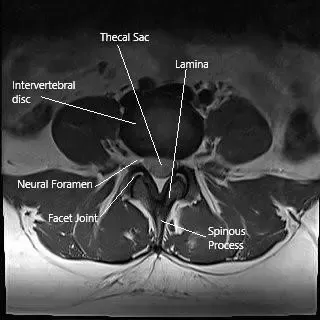

MRI image showing the axial section of the lumbar spine.

Sciatica is a collection of symptoms that occur due to compression or irritation of the spinal nerves L4, L5, S1, S2, and S3 that combine to form the sciatic nerve. Sciatica symptoms include buttock pain that may radiate down the back of the thigh, leg, or feet. The pain may be accompanied by pins and needles sensation.

The surgical treatment of sciatica comprises decompression of the structures, causing nerve root irritation and compression. The decompression may involve removing the disc material, removing the lamina, and may involve the fusion of the involved segment.